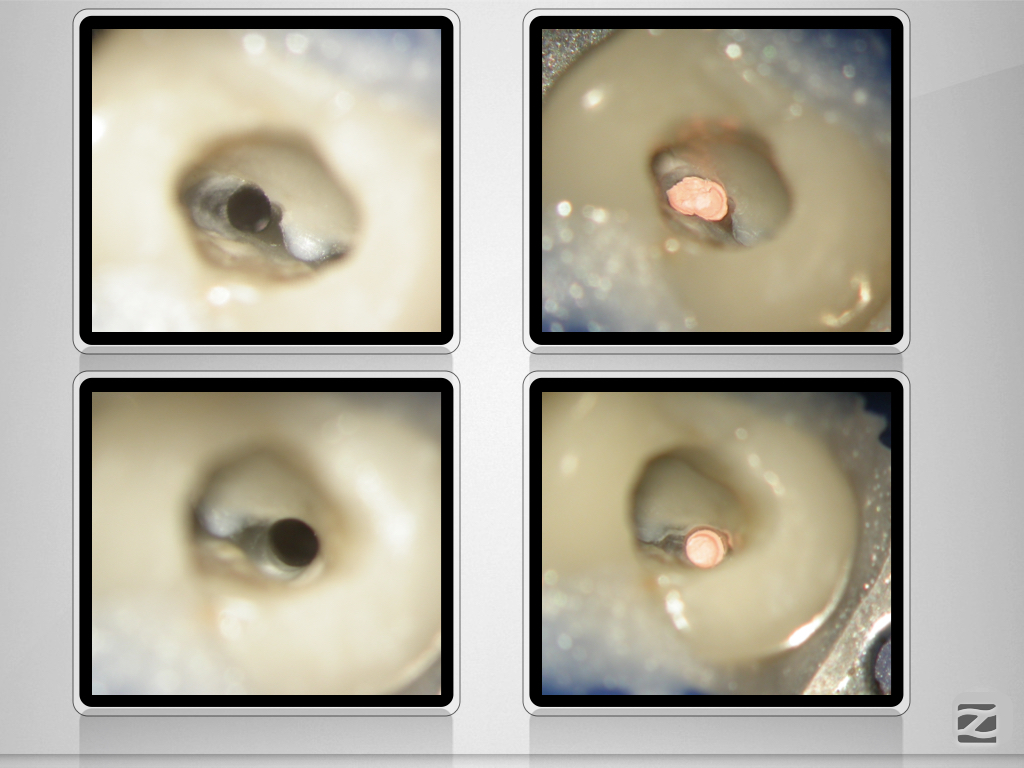

24D.009

Deutlich verfehlt